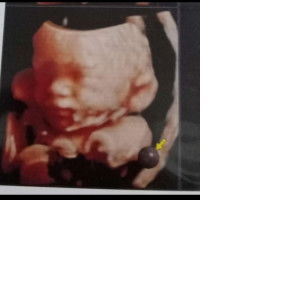

bunda disni ngidamnya aneh2 gak si? ak hamil udah 10week tp ngidam gak terlalu, mkn malah kuat banget. suami malah kebalikan , ampir sbln lebih sakit trs , pdahal bru smbuh udah sakit yg lain lgi , makannya bekurang kadang sedih liatnya.. kt orang suami yg ngidam bunda ada gak yg kayak gini !!